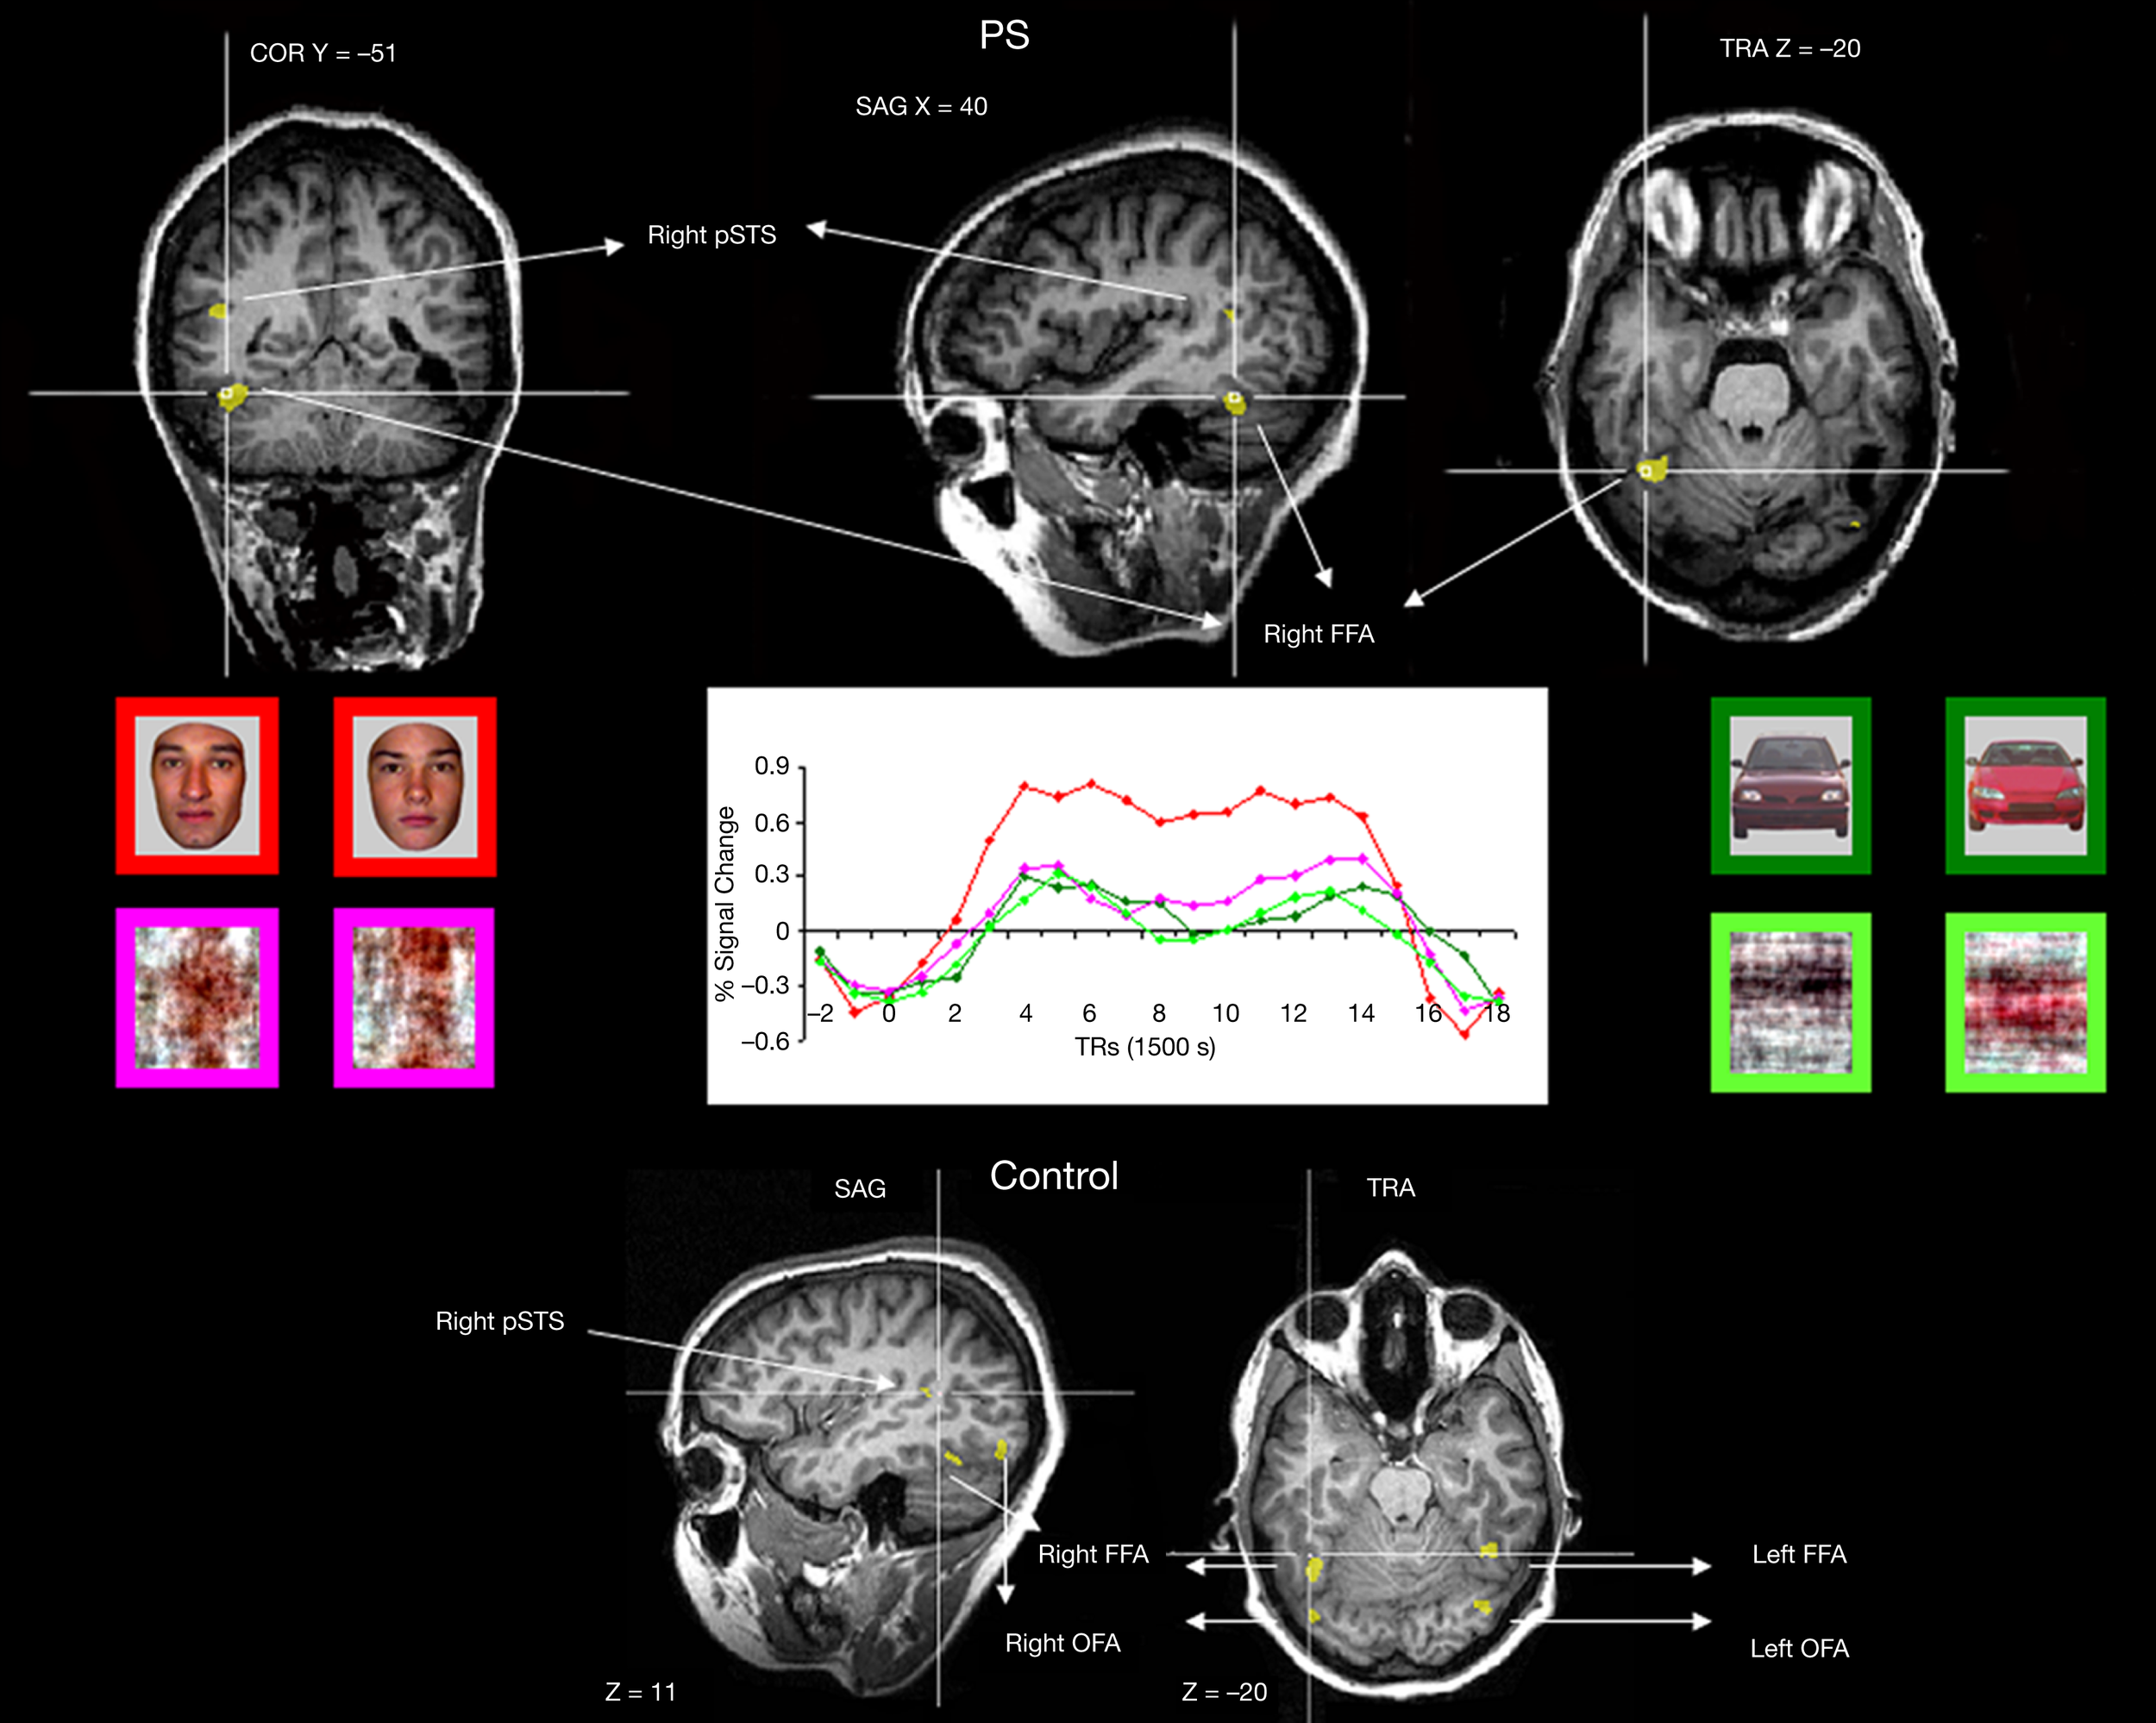

Figure 2

Functional brain areas disclosed in the face localizer experiment with faces, scrambled faces, pictures of cars and scrambled cars. The different areas (bilateral FFA, OFA, and right pSTS) are displayed below for a normal participant, and the intact part of this network is illustrated for the patient PS on top (right FFA, left OFA, right pSTS). Note the asymmetrical lesions, damaging the cortical territory of the right OFA and left FFA (for a full description, see Sorger et al., 2007).

In the localizer scan, normal participants showed activation (see Table A1 of Appendix for details) in the right and left FFA (mean Talairach coordinates: 36.7, −46.7, −19.1 and −40.9, −46.3, −19.6 respectively), in the right and left OFA (38, −78.4, −11.8 and −34.6, −73.6, −15.6, respectively) and in the right pSTS (43.1, −44.6, 9.2)4. For PS, consistent with previous observations, there were significant activations at [q(False discovery rate) < 0.05] to faces in the FFA and pSTS of the right hemisphere (36, −51, −21, and 45, −56, 10 respectively). These areas were normal in size and anatomical location as previously reported for normal observers and for PS (Rossion et al., 2003; Sorger et al., 2007; Dricot et al., 2008). There was also a small significant activation in the left inferior occipital cortex for PS [left OFA, at p(uncorrected) < 0.05, −40, −73, −19], as found in some previous studies of the patient (Sorger et al., 2007). In agreement with all these previous studies of the patient PS, even at the least conservative statistical threshold (p < 0.05 uncorrected) at which these two ROIS could be identified in every normal participant, there was no evidence of significant activation around PS’ lesions which could have been considered as a right OFA and left FFA (Table 1).

In summary, the missing components of the network of face-preferential activation in PS’ brain (left FFA and right OFA) were areas located in structurally damaged tissue (Figure 2). As shown previously (Rossion et al., 2003), the average localization of the right OFA in normal participants falls within the right inferior occipital lesion of the patient PS (Figure A2 of Appendix). Moreover, 9 out of the 11 individually localized right OFAs in the present study fall completely or largely within the territory of PS’ right inferior occipital lesion.

In the fMRI experiment with Mooney faces, PS was again as accurate as control participants (72.8%; control group average is 69.1%, SD = 8.5%;t6 = 0.41; p = 0.35; AM: 83%; Crawford and Garthwaite, 2002) and as fast (1384 ms, controls’ average = 1216 ms, SD = 335 ms; t6 = 0.89; p = 0.21; AM: 1000 ms).In normal participants (random effect group analysis, Mooney upright − Mooney inverted; dl = 6), we found a significant effect in the two right hemisphere higher order “face areas” (FFA, pSTS), but not in the left OFA (FFA, t = 3.33, p < 0.016; pSTS, t = 3.59, p < 0.012; left OFA, t = 1.15, p = 0.30; Table 1; Figures 4A and 5 and Figure A3A of Appendix).

Figure 5

Among the face-sensitive areas that are intact in the prosopagnosic patient's brain, only the right FFA, and the pSTS to a lesser extent, present a larger response to Mooney stimuli perceived as faces as compared to the same pictures presented upside-down (“non-faces”). Similar findings are made control participants (S1 illustrated), PS and the age-matched control (AM). The left OFA does not show any enhanced response to the Mooney face stimuli.

The exact same results were found in the individual analysis of PS: right FFA (t = 3.873, p < 0.0001), pSTS (t = 2.751, p < 0.0060), left OFA (t = −1.201, p = 0.23), and for the age-matched participant (AM: FFA, t = 2.73, p < 0.0064; pSTS, t = 3.69, p < 0.0002; left OFA, t = −1.93, p = 0.05; Figure 4).

In the right OFA, located in a region of cortex structurally damaged in PS’ brain, control participants showed no significant advantage for upright compared to inverted Mooney faces (t = −0.28, p = 0.79; AM: t = −2.21, p = 0.03; Figure 4A). However, the contrast was also significant in the left FFA (also lesioned in PS’ brain) in the group of normal participants (t = 3.17, p < 0.019; Figure A3A of Appendix), but it was not significant for the AM participant (t = −1.17, p = 0.24).

In summary (Table 1), independently of whether the analysis was computed on correct trials or on all trials, we found significant activations to the perception of Mooney faces primarily in the right FFA and right pSTS in the normal population. Strikingly, identical observations were made for the PS. In the left inferior occipital cortex, structurally intact in PS’ brain and where a face-sensitive response (left OFA) was found in the localizer, there was no evidence for sensitivity to faces presented as Mooney stimuli, neither for the normal controls nor for PS. Finally, in the two regions that are structurally damaged in PS’ brain, there was little (left FFA) or no (right OFA) evidence for sensitivity to the categorization of a Mooney stimulus as a face in the normal population.